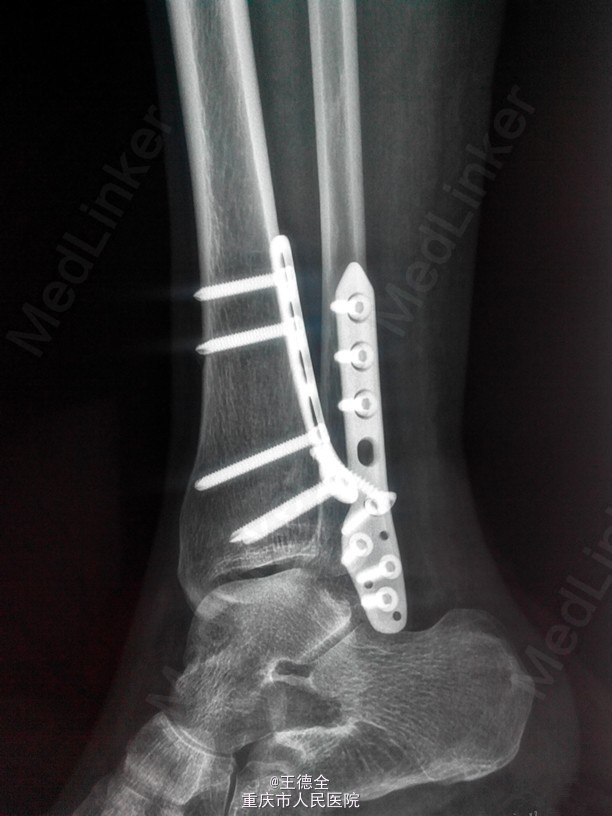

外踝及后踝骨折一例

患者女,44岁,车祸致右踝关节疼痛,肿胀,活动受限入院。肿胀消退后于手术治疗,选择后外侧入路做一个切口,克氏针临时固定,最终钢板固定。